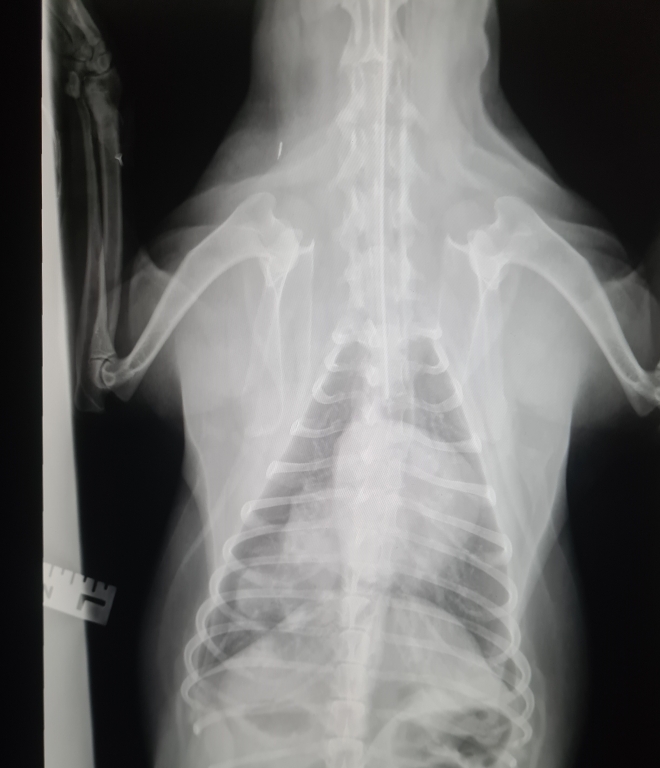

Detailed examinations at WMR had found a mass caused by a rare inflammatory pulmonary disease obstructing the entire left side of her chest, which was subsequently putting a major strain on her right lung.

Julie said: “After an initial x-ray at our local vets, it was decided Tilly needed a soft tissue consultation for a more detailed examination.

Chris Lancelott, veterinary surgeon at WMR who led the complex lung removal operation, said: “Tilly had an abnormal growth. It’s involvement with the primary air tube meant that removal of all of the left lung lobes which were extremely close to the windpipe was required and was not without risk.